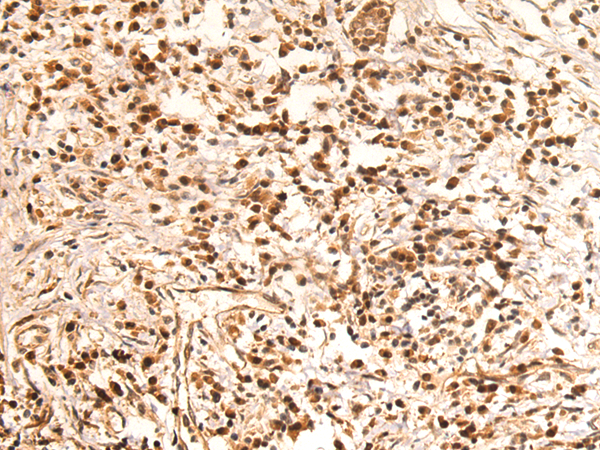

分类: 科研抗体货号: P10609别名: TRAP; CATC4; PCTAIRE2BP应用: IHC反应种属: Human, Mouse, Rat